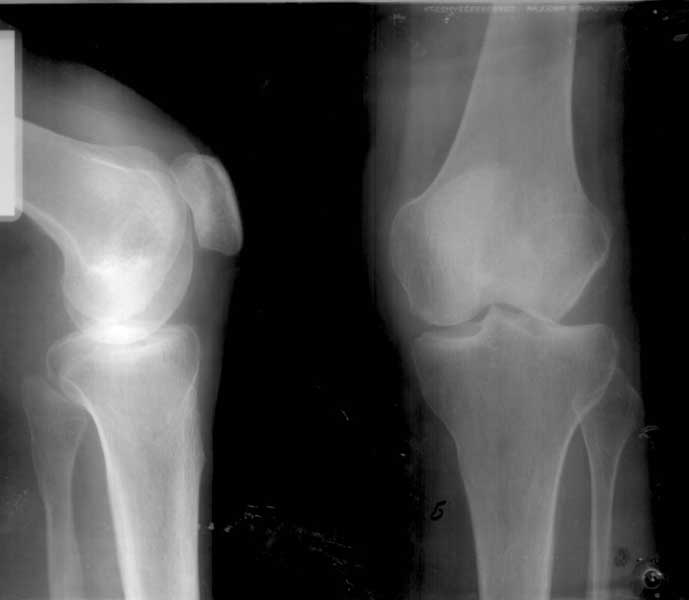

At the present time a post traumatic defect of lateral femoral condyle is observed. On the X-rays of left knee, a lateral femoral condyle defect is observed up to the 1/3 of the joint surface. Clinical examination of left knee joint revealed moderate atrophy of the muscles of left femur and shin, moderate pain with palpation of the lateral joint line, pathological deviation of the shin to the outside up to 20 degrees at doing the clinical tests, accompanied by the appearance of moderate pain, motions in the knee joint are slightly restricted.